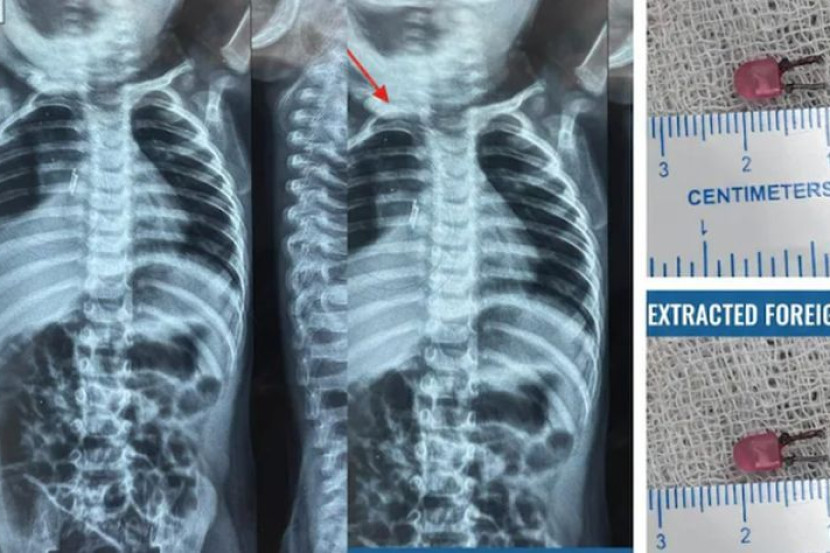

Doktor berjaya mengeluarkan sebiji mentol LED kecil yang tersangkut di saluran pernafasan kanak-kanak berkenaan. -Foto NDTV

Prosedur bronkoskopi dijalankan dan doktor berjaya mengeluarkan sebiji mentol LED sepanjang satu sentimeter yang tersangkut di saluran pernafasannya.